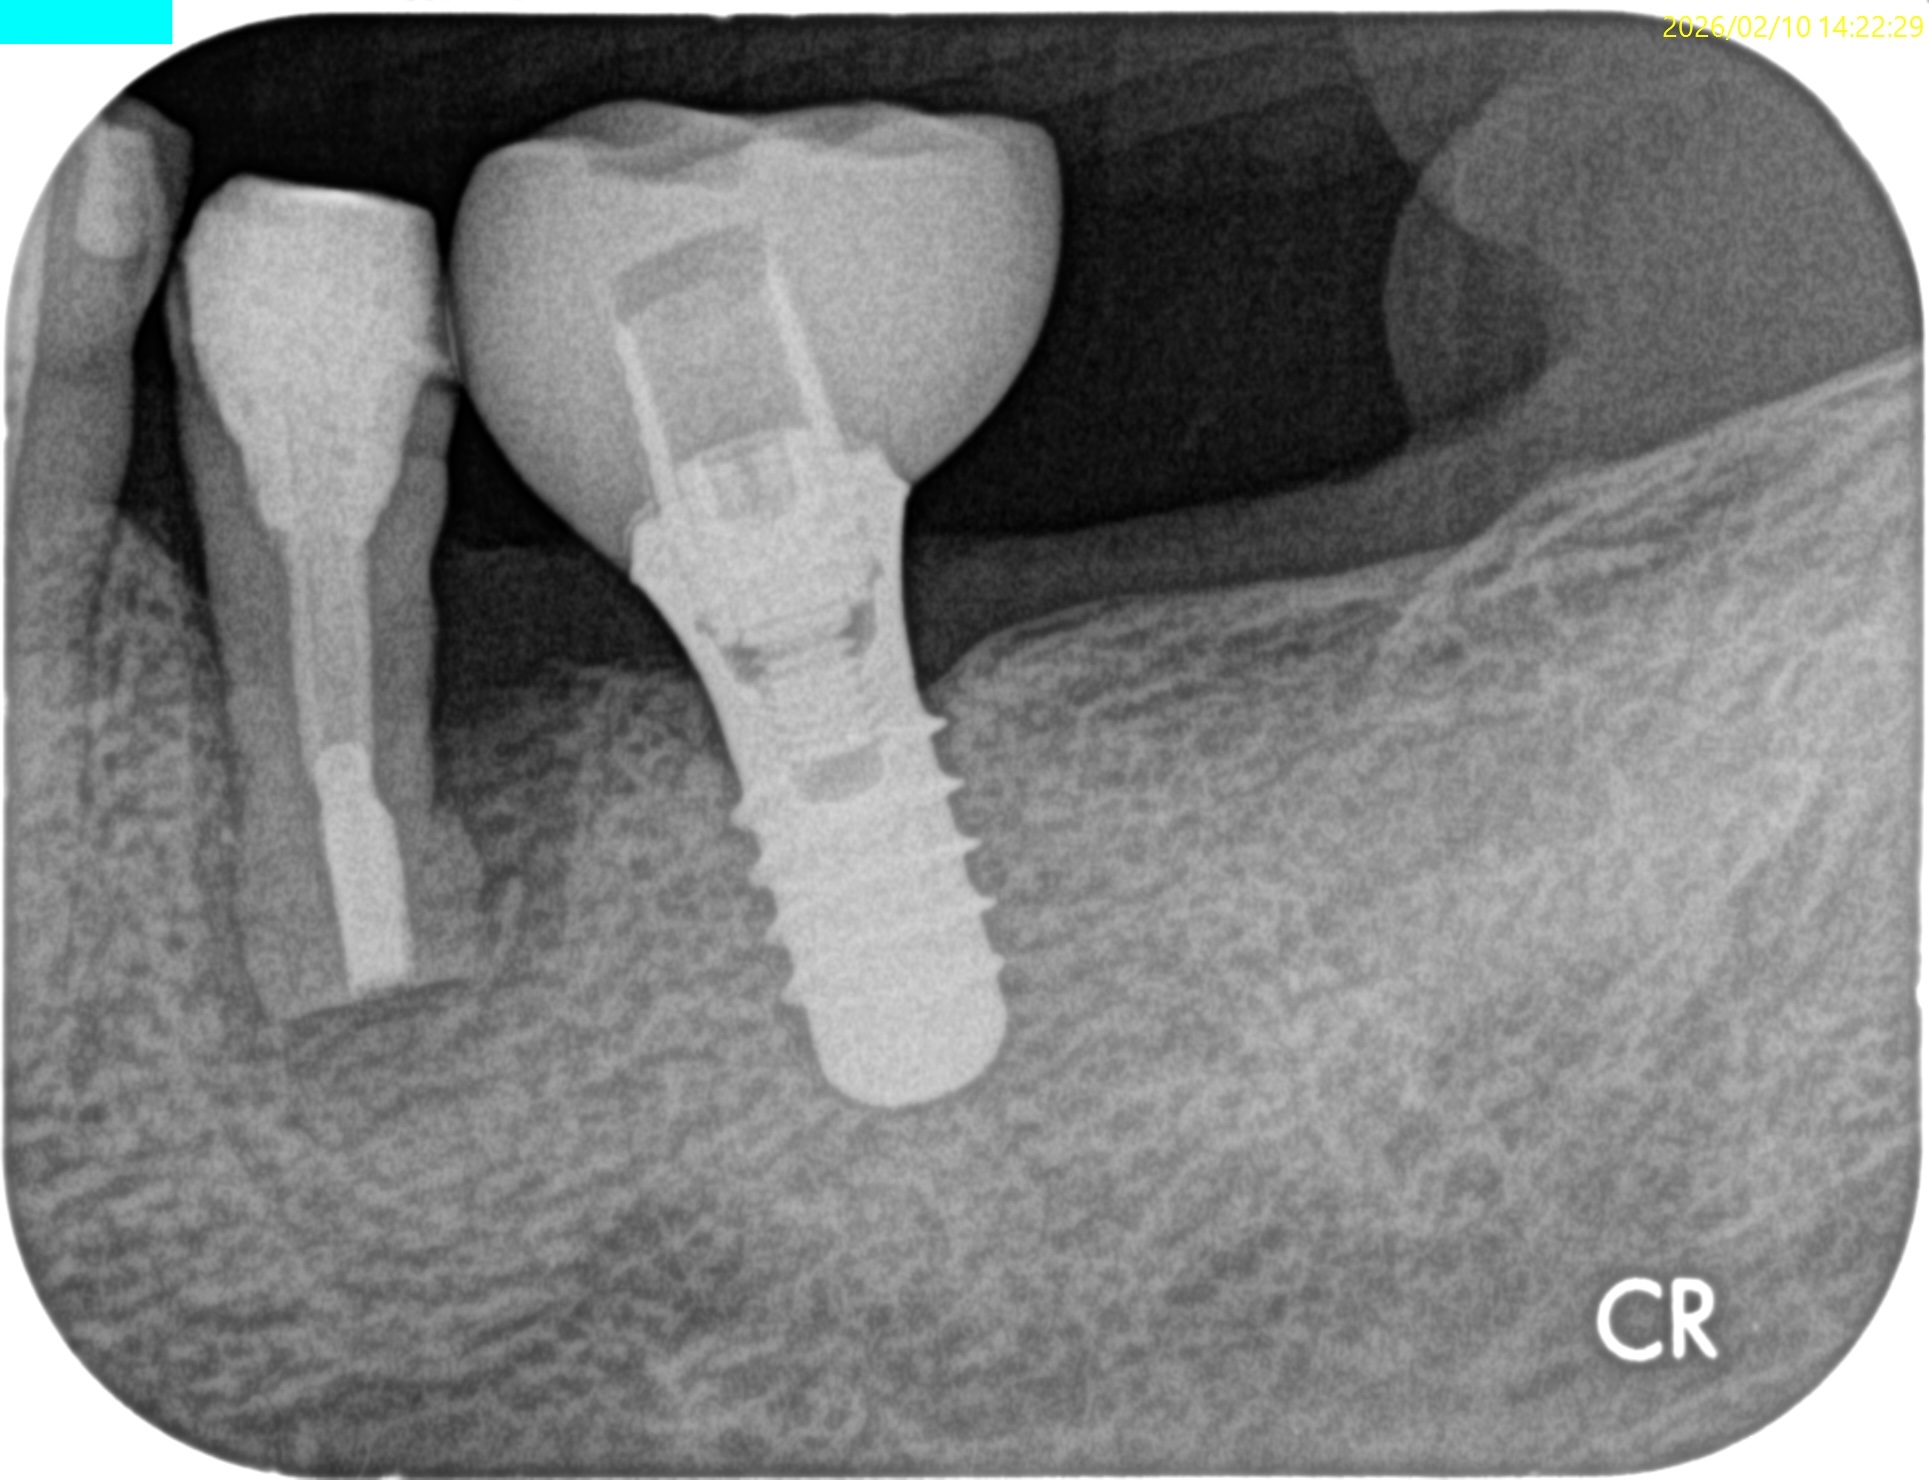

昨日の処置の後、#20 Intentional Replantationを行っていた。

頬側の皮質骨は既にない。

VRFを想像させる絵だが、

術前の歯周ポケット測定では、#20は全周、Within Normal Limit(正常の範囲内)である。

術後にPAを撮影した。

術後にPA, CBCTを撮影した。